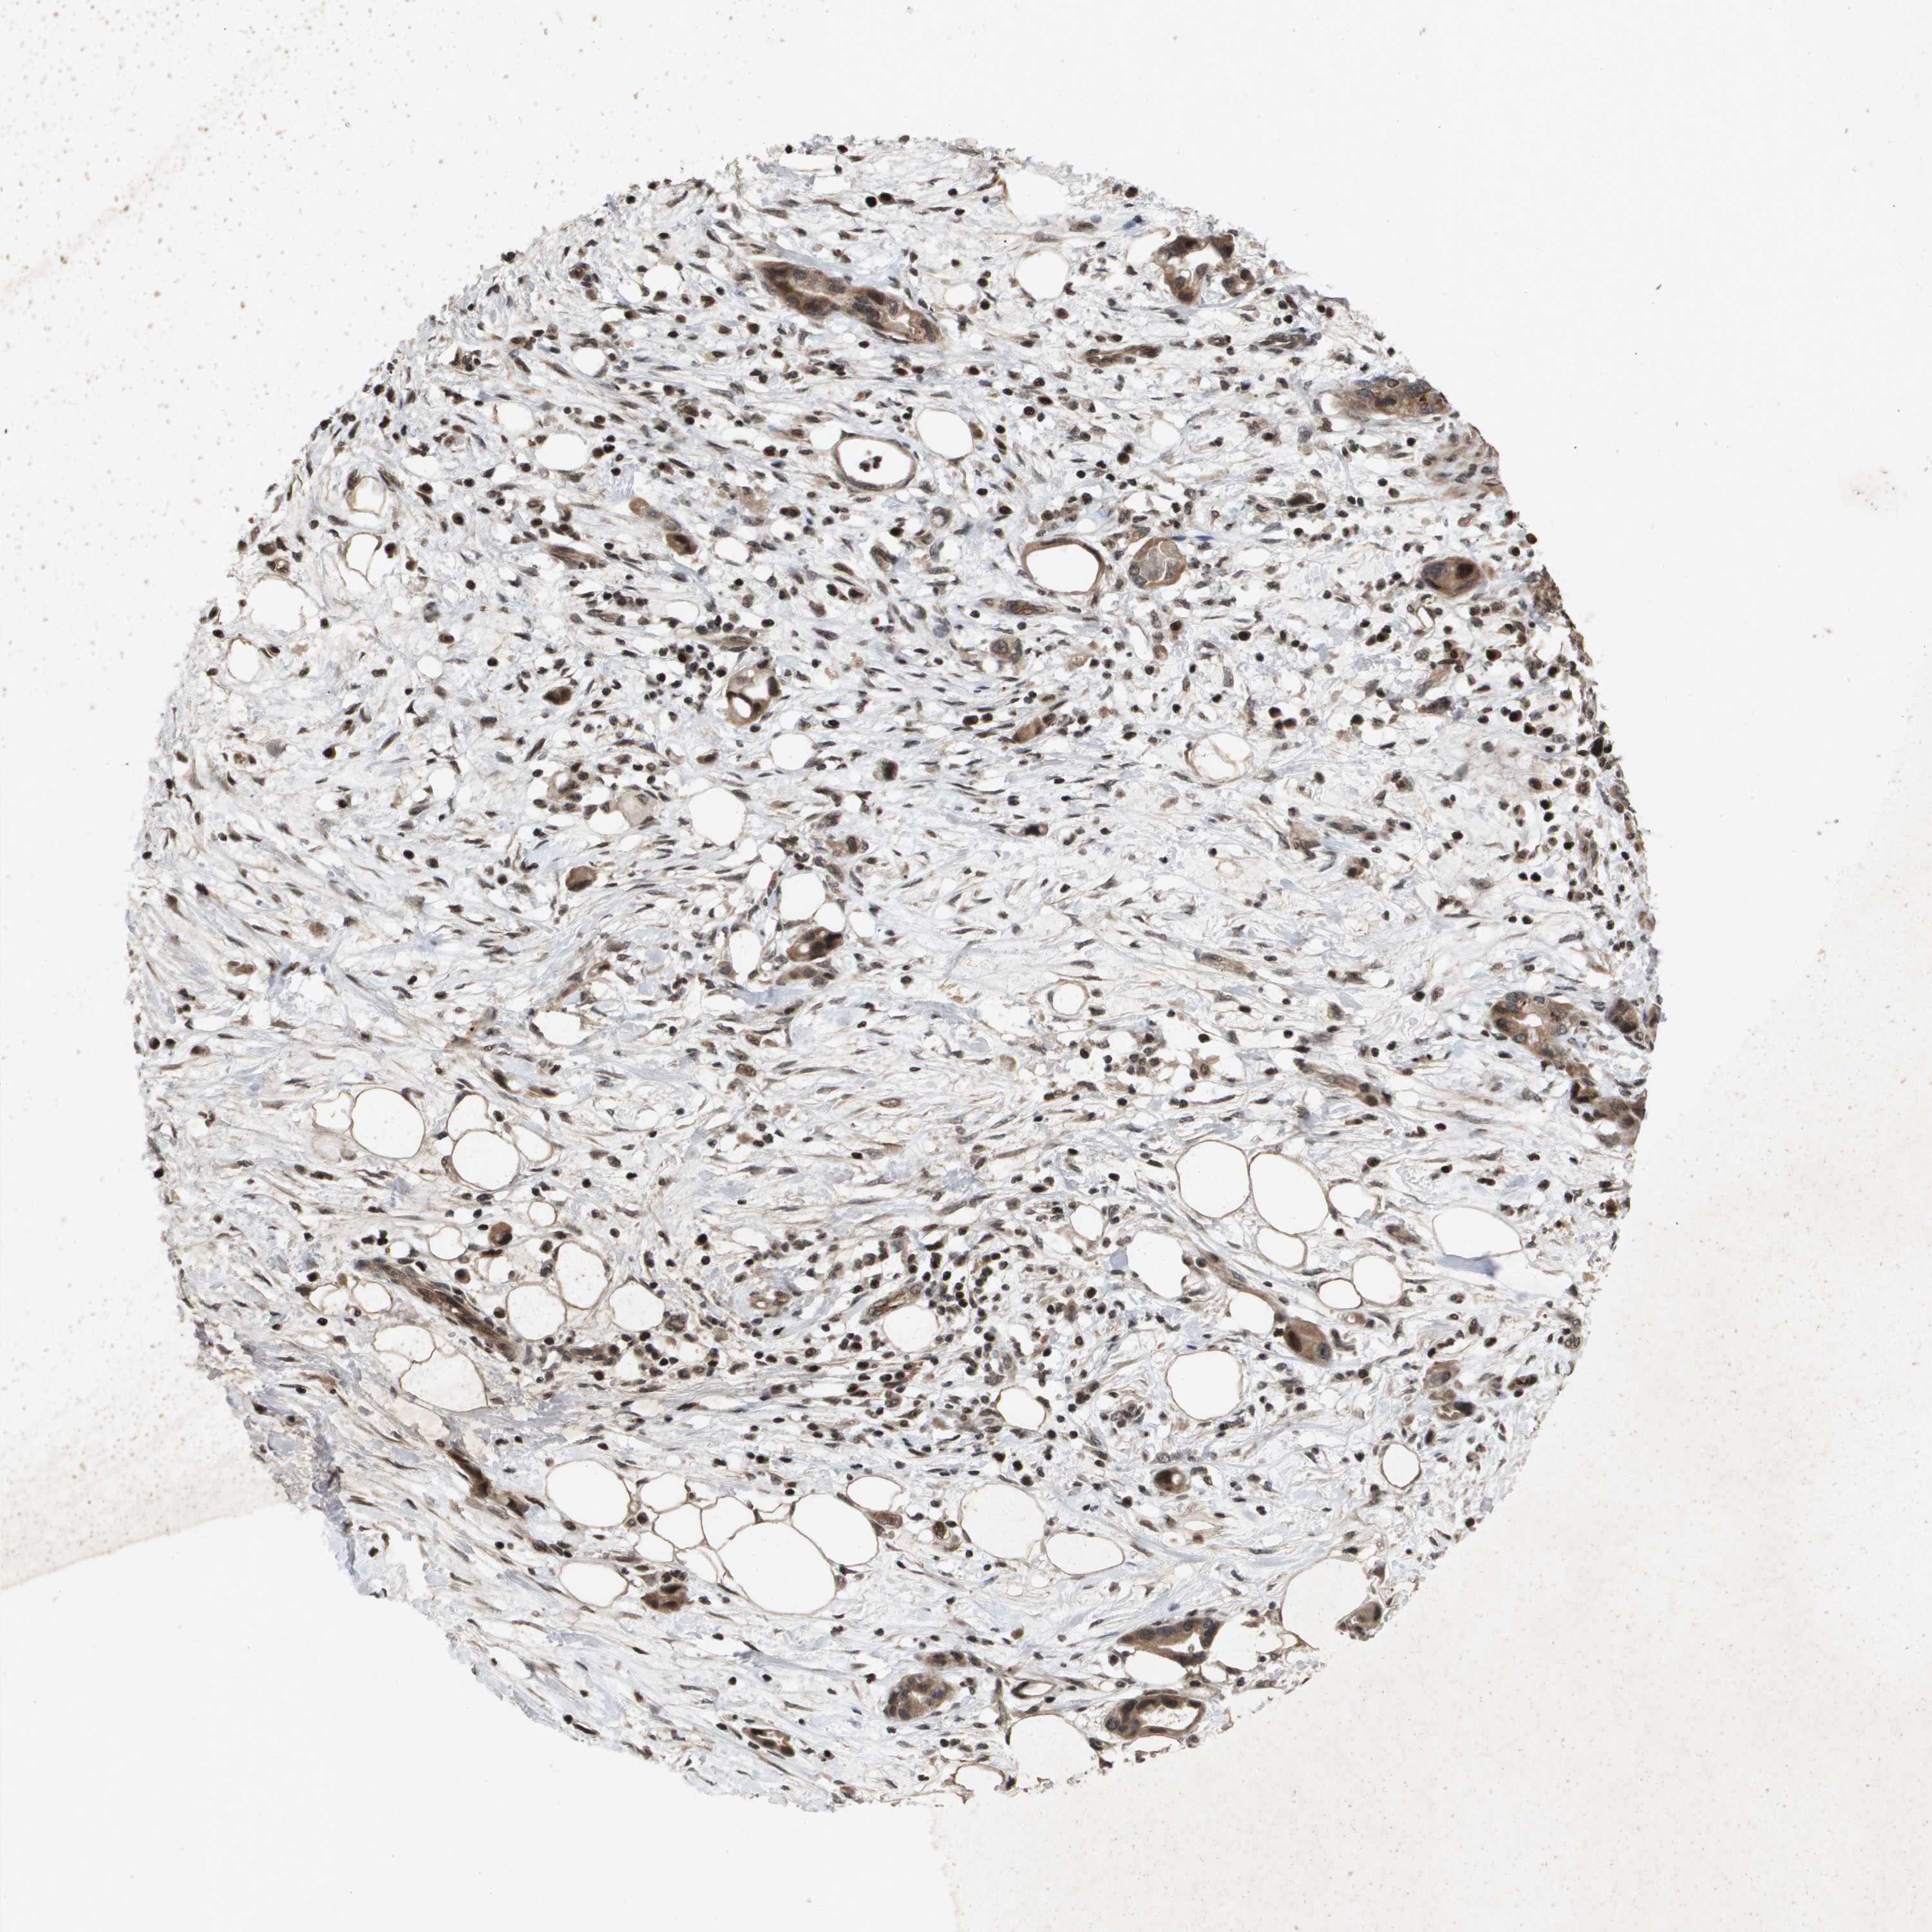

PANCREATIC CANCER - Protein expressioni

A mouse-over function shows sample information and annotation data. Click on an image to view it in a full screen mode. Samples can be filtered based on level of antibody staining by selecting one or several of the following categories: high, medium, low and not detected. The assay and annotation is described here.

Note that samples used for immunohistochemistry by the Human Protein Atlas do not correspond to samples in the TCGA dataset.

Antibody stainingi

Antibody staining in the annotated cell types in the current human tissue is reported as not detected, low, medium, or high, based on conventional immunohistochemistry profiling in selected tissues. This score is based on the combination of the staining intensity and fraction of stained cells.

Each image is clickable and will lead to virtual microscopy that enables deeper exploration of all samples and also displays staining intensity scores, fraction scores and subcellular localization as well as patient and tissue information for each sample.

Antibody HPA028549

Antibody HPA052504

Antibody CAB017452

Staining

High

Medium

Low

Not detected

Intensity

Strong

Moderate

Weak

Negative

Quantity

>75%

75%-25%

<25%

None

Location

Nuclear

Cytoplasmic/membranous

Cytoplasmic/membranous,nuclear

Adenocarcinoma, NOS